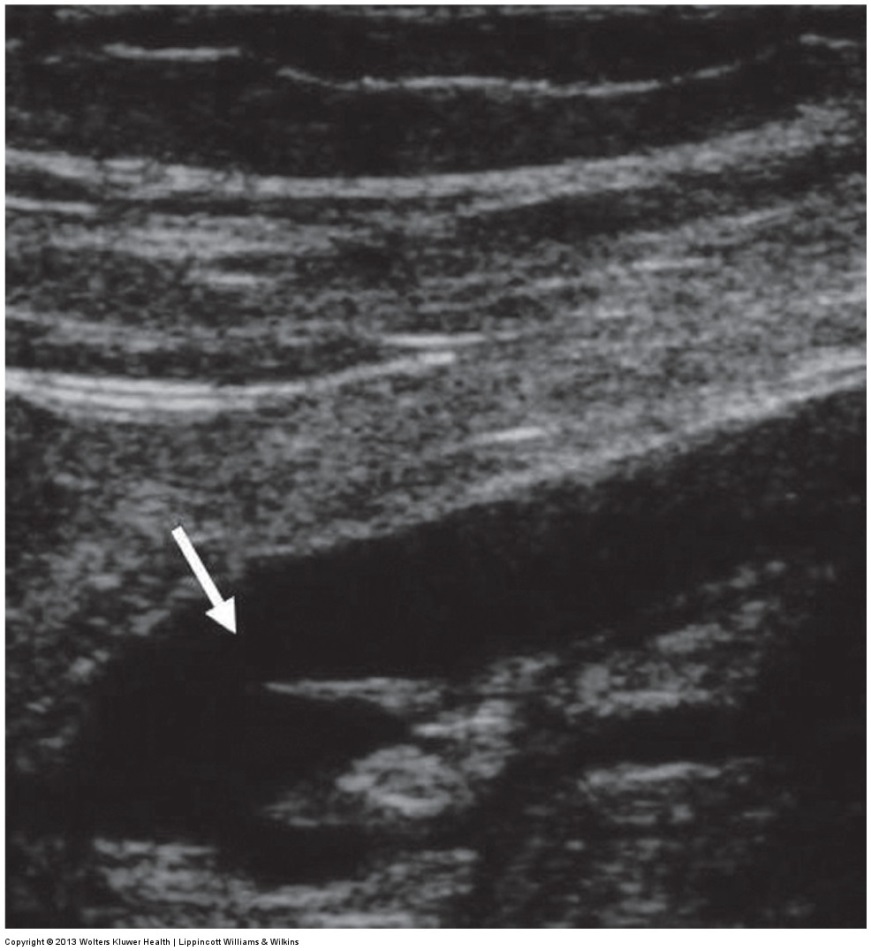

ultrasound image of thrombus next to valve leaflets

ultrasound of superficial varices with the main system beneath it

ultrasound image of a thickened recanalized vein

ultrasound of the SSV with wall calcification

ultrasound image of a frozen valve leaflet